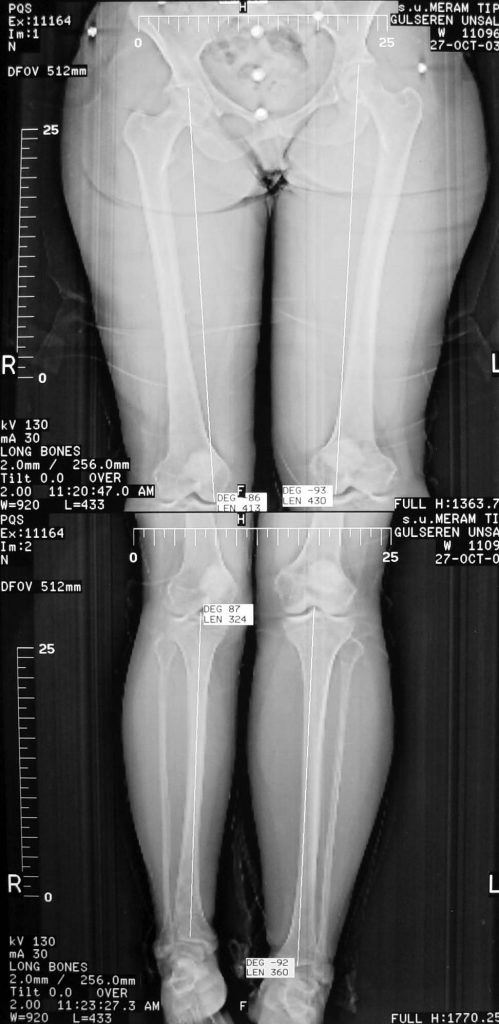

Case 2